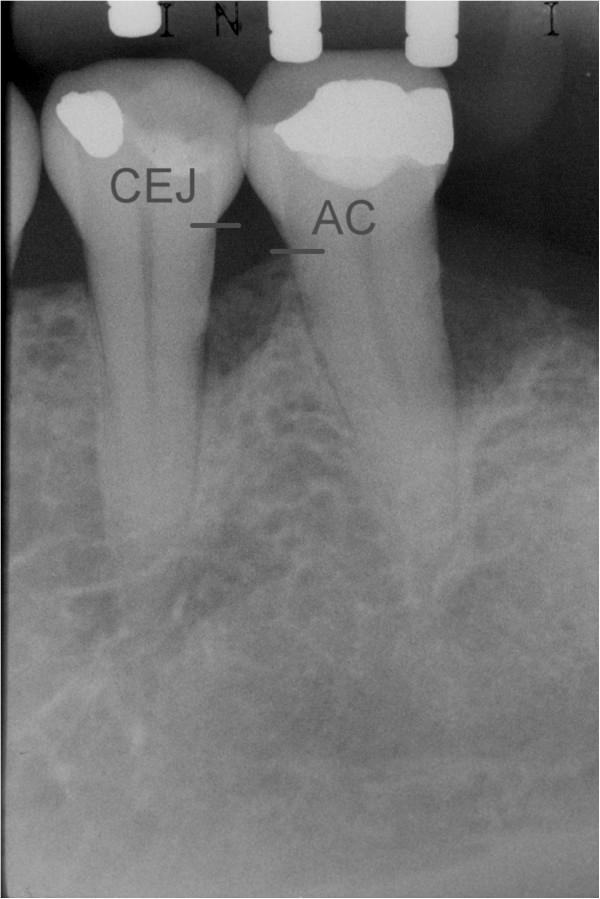

This split-mouth, double-blind randomized controlled trial evaluated radiographic changes in infrabony defects treated with open flap debridement (OFD) or OFD associated with enamel matrix derivative (EMD) after a 24-month follow-up. The radiographic distance from the CEJ to the bottom of the defect (BD) was considered the primary outcome. CEJ-BC and defect angle were secondary outcomes.

Ten patients presenting 2 or more defects were selected. An individualized film holder was used to take standardized radiographs of the 43 defects, at baseline and after 24 months. Images were digitized and used to measure the distances from the cemento-enamel junction (CEJ) to the alveolar crest (AC), CEJ to the bottom of the defect (BD) and infrabony defect angle. Statistical analysis was performed in SPSS for Windows (version 5.2). Paired samples t test was used to compare test and control groups and to evaluate changes within each group. The level of significance was set at α = 0.05%.